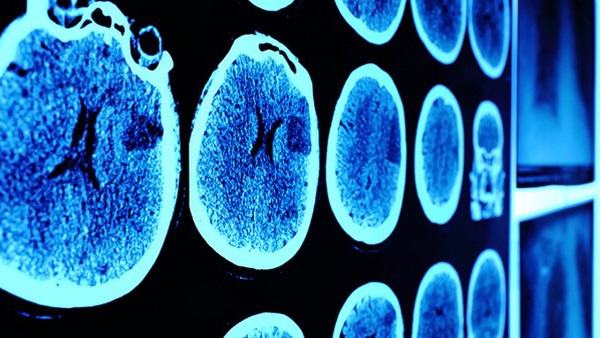

其次,老年脑萎缩主要表现为脑容量减小,大脑皮质变薄,并伴随着与认知相关的问题,如记忆力下降、思维迟钝等。小脑萎缩主要影响小脑,导致小脑体积缩小,进而影响身体运动和平衡控制。患者可能会出现手臂和腿部肌肉无力、协调障碍、共济失调等症状。

综上所述,老年脑萎缩和小脑萎缩是不同类型的脑部退化疾病。老年脑萎缩主要表现为大脑的退化和与认知有关的问题,而小脑萎缩则主要影响小脑,导致运动和平衡控制异常。虽然二者有一些相似之处,但由于发病原因、症状表现和治疗方法不同,需要根据具体情况进行正确的诊断和治疗。